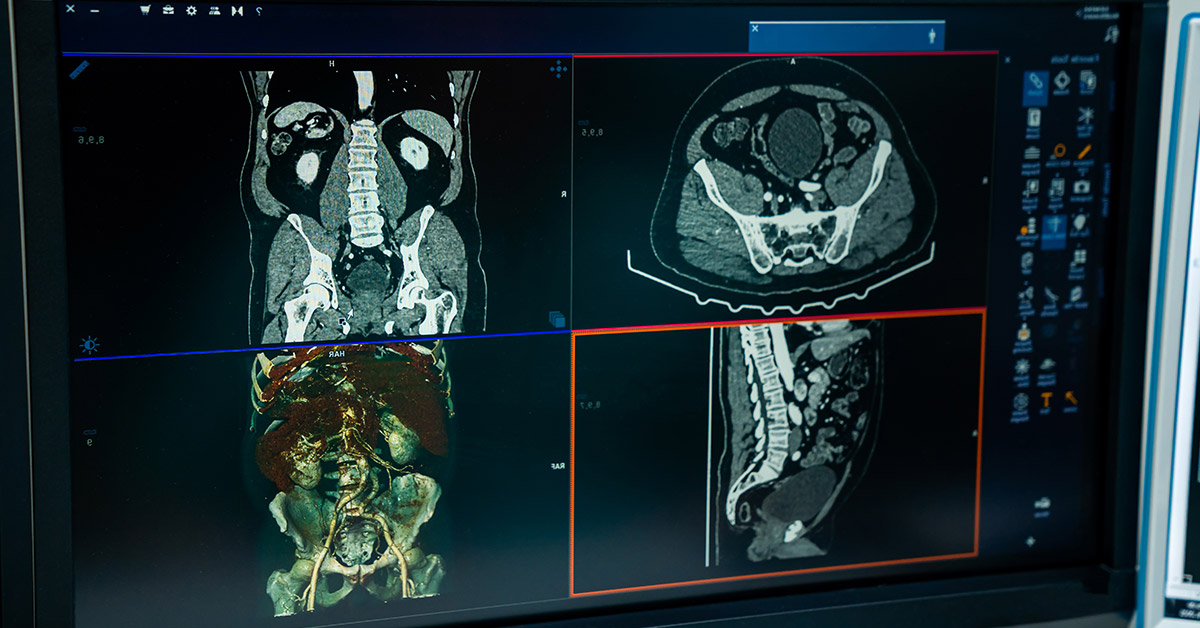

Algoritmos para análise de TC e RX para detecção de COVID-19, integrados à plataforma RadVid19.

Triagem de exames de tomografia para priorizar casos suspeitos de lesões hepáticas.